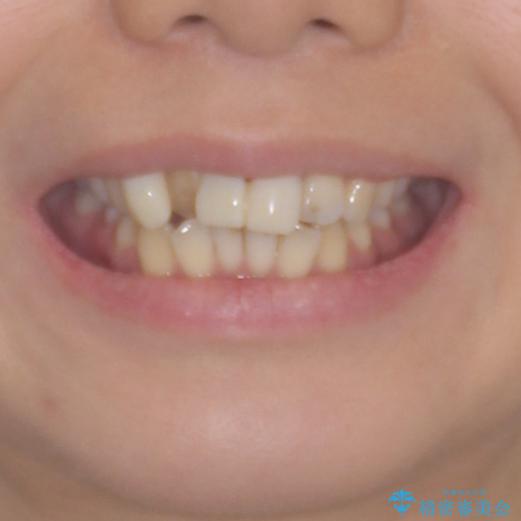

補助装置により上顎歯列を遠心移動させたため、非抜歯でしたが口元の突出感をある程度改善させることができました。

欠けてしまった前歯もオールセラミッククラウンにて自然に補綴することができました。